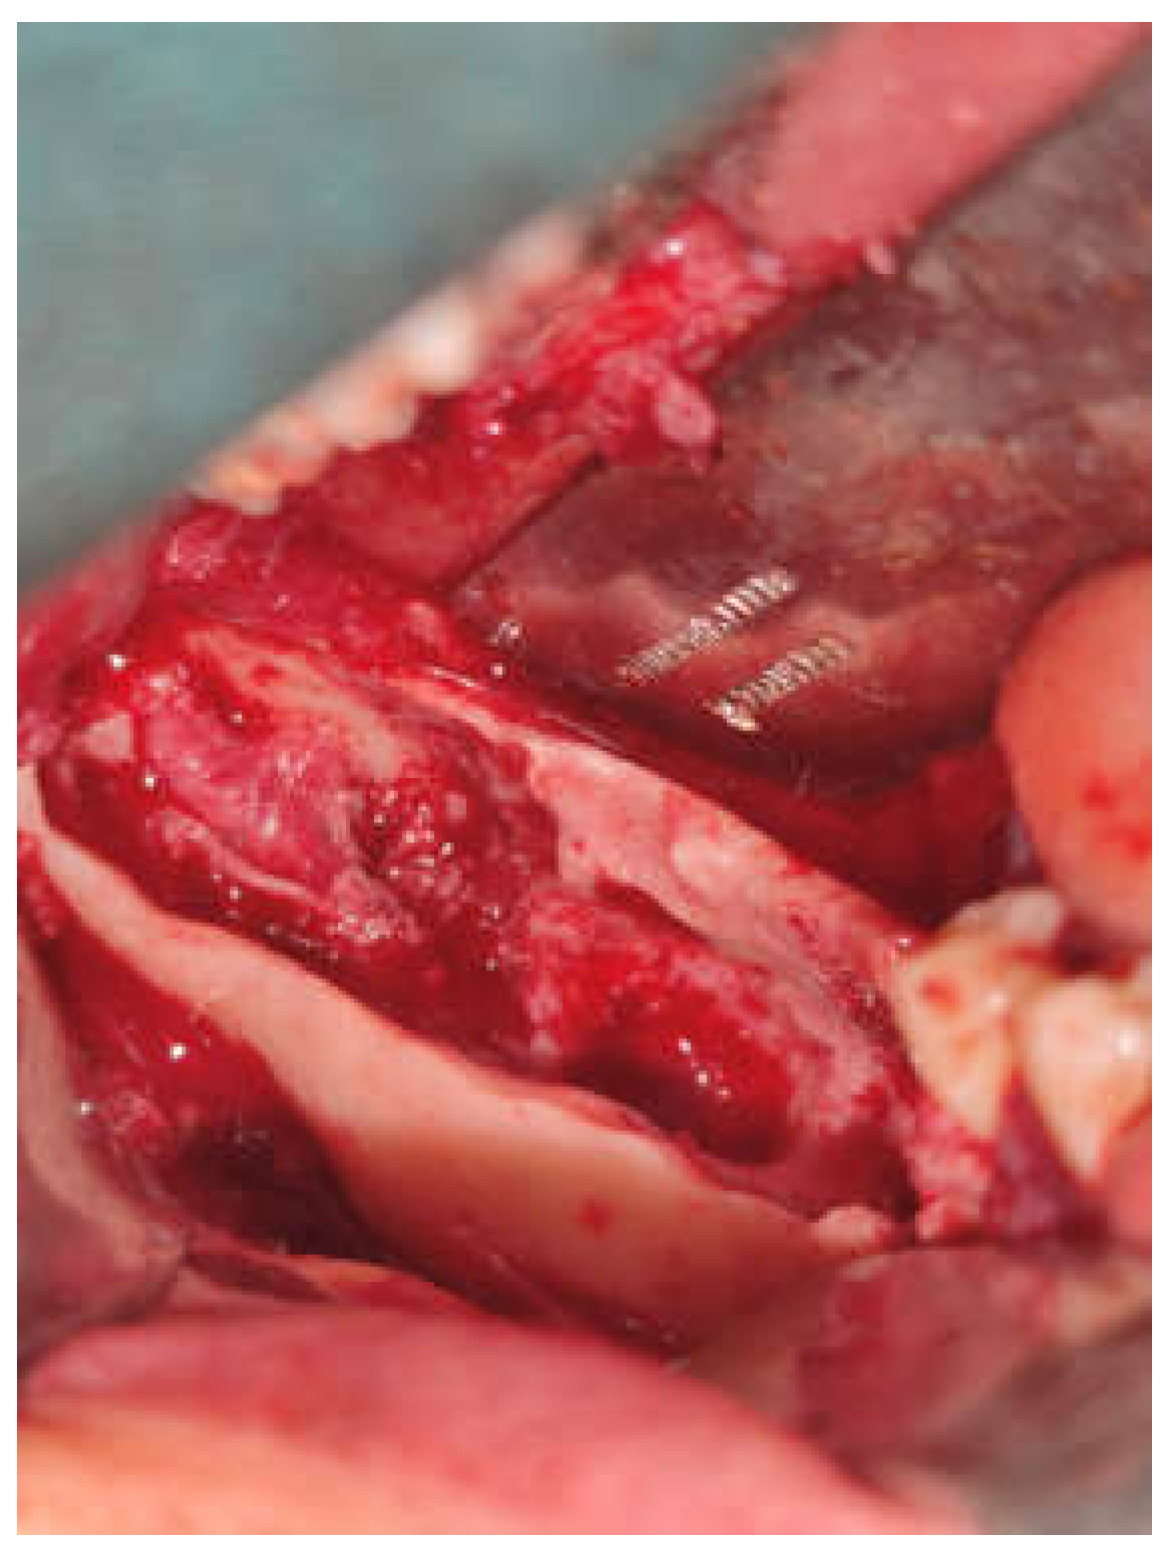

Figure 1. OPG showing preoperative lesion related to Impacted lower 3rd molar tooth in right side of mandible.

A 22-year-old female patient reported to our outpatient department with a chief complaint of swelling in the lower right region of the body of the mandible for 4 years. Cone beam CT (CBCT) revealed the extent of the lesion and the loss of cortical bone on both the lingual and buccal sides, along with a thinning of the bone base. Furthermore, the inferior alveolar nerve (IAN) canal was affected and measured approximately 20.5*26.2 cm after previous marsupialization. The patient observed swelling and misalignment of the teeth in the lower right posterior area and reported experiencing pain in that same region. The pain was dull and aching, occurring intermittently, worsening during chewing and easing with rest. During the extraoral examination, a diffuse swelling was noted on the lower third of the face, extending to the right side, measuring about 4 × 4 cm. The skin over the swelling appeared normal, with no visible pulsations or discharge. On palpation, the swelling was firm. The preliminary diagnosis was an odontogenic dentigerous cyst or ameloblastoma. A small sample of the cyst wall was collected for histological analysis. The cystic membrane was marsupialized, and a tube was inserted into the cavity to ensure it remained open. In the first month after surgery, the surgical site was rinsed weekly, followed by monthly follow-up visits at the clinic. The histological report supported a diagnosis of mural unicystic ameloblastoma. The marsupialization procedure was kept in place for three years, during which the cortical rim of the mandibular canal remineralized, and new bone formation and cortical borders developed. A second surgery was scheduled, during which an envelope flap and bone removal—similar to the procedure for impacted tooth extraction—were performed to gain access to the lesion. This approach facilitated the enucleation of the ameloblastoma, involved scraping the bone walls to eliminate any potential ameloblastic infiltrates, and included extensive irrigation with garamycin antibiotics, followed by graft augmentation in the defect. The surgical specimen was sent for histological analysis, and the pathologist confirmed a diagnosis of UA with mural growth.